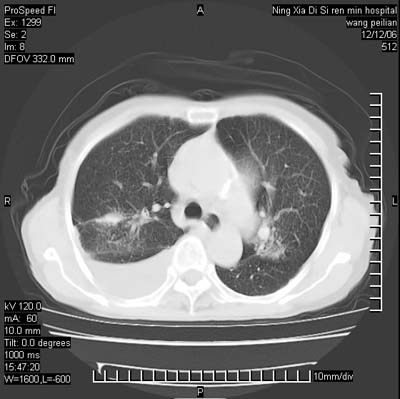

标题: CT5609:胸部:女77 病史不详 [打印本页]

标题: CT5609:胸部:女77 病史不详

两肺可见多个大小不等的结节,左侧有胸水,纵隔淋巴结增大,考虑是细支气管肺泡癌

两肺尖纤维索状影,两下肺结节块状影,且有钙化灶,右胸腔积液。考虑肺结核并胸膜炎。

双侧肺结核伴右侧胸腔积液.

两肺尖纤维索状影,两下肺结节块状影,且有钙化灶,右胸腔积液。考虑肺结核并胸膜炎肺间质纤维化

从图中见许多致密的结节影,,增强后明显强化,考虑血管炎症肉芽肿.当然还有慢支并小叶中央型肺气肿以及陈旧结核,胸腔积液.

考虑:1、慢性支气管炎合并全小叶型肺气肿、间质纤维化;

2、双肺结核;

3、右侧胸膜炎(积液)。

1、双肺继发型肺结核(以纤维、增殖灶为主);

2、右侧胸腔积液;

3、其余符合老年肺改变。

考虑两肺结核,右侧胸膜炎(积液)

双肺见多个结节状及条索状影,双侧胸腔积液,右侧叶间积液,考虑结核性胸膜炎

肺结核并右侧结核性胸膜炎